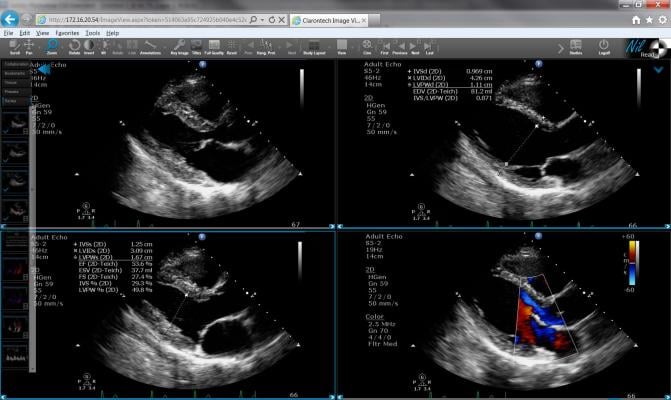

Filled with original illustrations, instructive videos, and detailed instructions to provide an effective resource for all echocardiographers, this document gives a comprehensive view of scanning techniques and protocols for today’s cardiovascular imaging.

The document includes an abundance of figures and illustrated tables, plus over 100 videos, in an effort to thoroughly define and demonstrate the various scanning maneuvers and image optimization techniques recommended for sonographers when performing an exam. “As the writing committee surveyed available resources, we found a lack of updated information, as well as a lack of consensus, in how to define all the different scanning techniques,” noted Mitchell. “Our hope is that this will provide a valuable resource for students and new sonographers, and that echo labs will use these new recommendations as a starting point to design comprehensive protocols that best fit the patient populations they serve.”